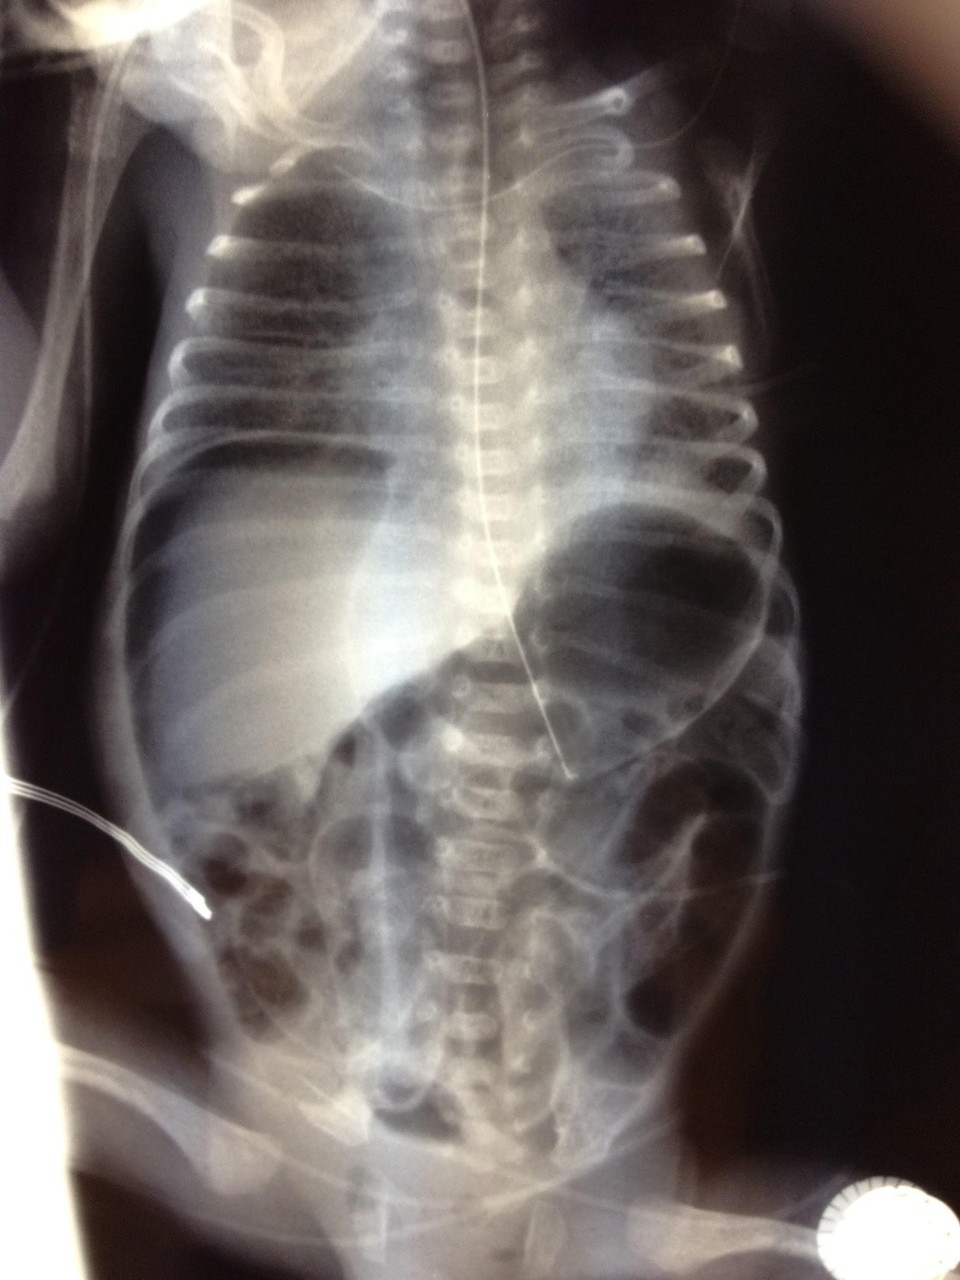

Peut compliquer la ventilation à haute pression nécessaire pour maintenir un volume courant élevé. À éliminer par une radiographie de thorax